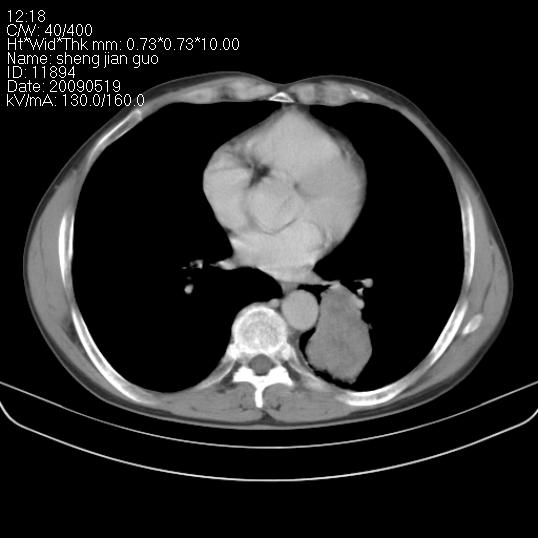

以下是引用zjzjr在2009-5-19 17:25:00的发言:[br]支持楼主考虑,另左肺下叶阻塞性炎症。

以下是引用zhao_bin2008在2009-5-19 17:48:00的发言:[br]支持左肺下叶周围型肺癌并阻塞性肺炎。

以下是引用zsl6918在2009-5-20 7:10:00的发言:[br]左侧中心型肺癌!